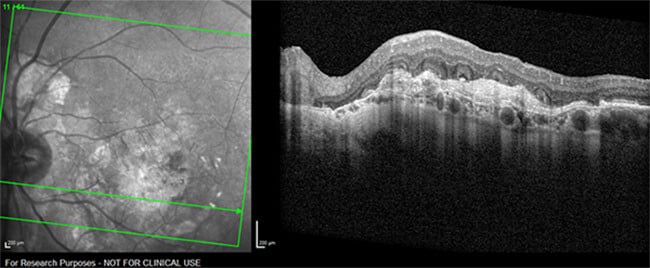

Simultaneous IR+OCT of ORT (arrow)

Image courtesy: Rosa Dolz-Marco, MD, Valencia, Spain